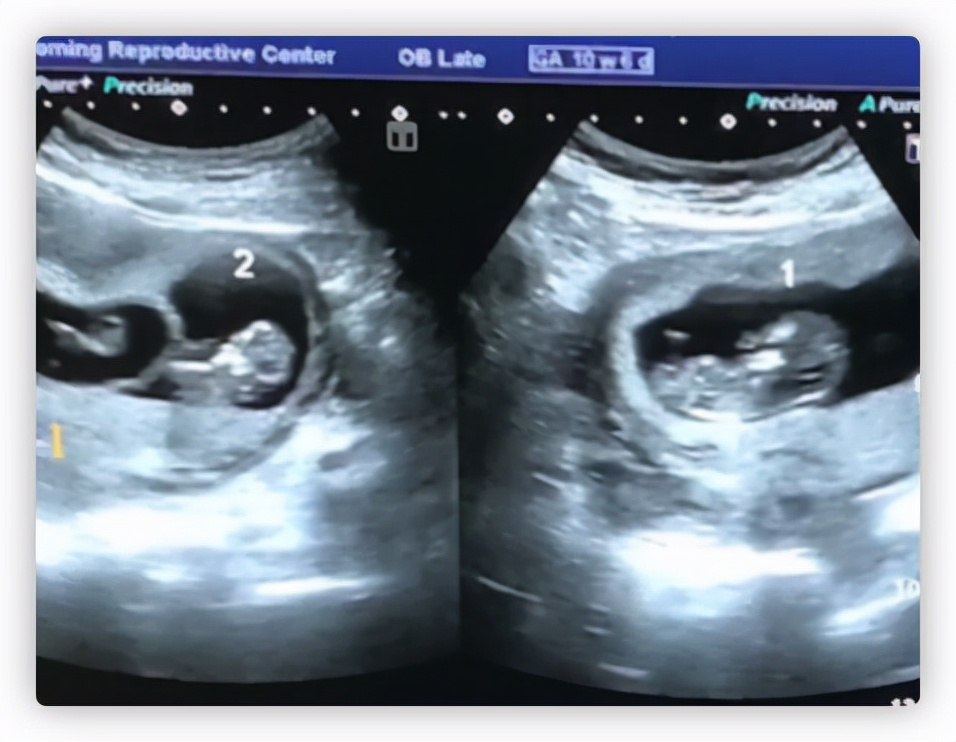

就在去年他们要放弃希望的时候 , 事情终于迎来了转机 , 当时明金成的妻子在一位名医的帮助下怀上了一对双胞胎 , 明金成激动不已 , 还专门在社交网站上晒出了自己的B超片子 , 激动落泪 , 让其他网友都感同身受的为他点赞 。 在妻子怀孕后 , 明金成经常带着他一起去医院楼下的花园里转圈、散心 , 还专门为她打造学会做菜 , 打造营养餐和玉米羹 , 可以说是无微不至的照顾她 , 给她宽阔的肩膀予以依靠 。